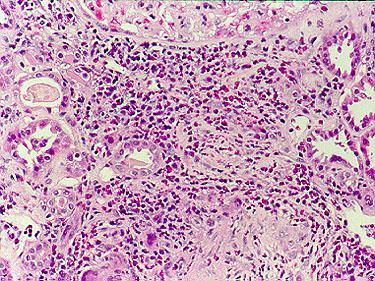

- Гистологические признаки васкулита с внесосудистыми скоплениями эозинофилов;

При постановке диагноза нужно исключить другие возможные заболевания, прежде всего узелковый полиартериит, гранулематоз Вегенера, хроническую эозинофильную пневмонию, идиопатический гиперэозинофильный синдром и микроскопический полиангиит. Окончательный диагноз устанавливается по результатам биопсии пораженной ткани.